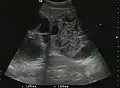

They can be single or multiple, with variable size, generally less than 20 mm (congenital). Rarely, sizes can reach several centimeters, leading up to the substitution of a whole liver lobe (acquired, parasitic). They may be associated with renal cysts; in this case the disease has a hereditary, autosomal dominant transmission (von Hippel Lindau disease).

The ultrasound appearance is a well defined lesion, with very thin, almost unapparent walls, without circulatory signal at Doppler or CEUS investigation. The content is transonic suggesting fluid composition. The presence of membranes, abundant sediment or cysts inside is suggestive for parasitic, hydatid nature. Posterior from the lesion the acoustic enhancement phenomenon is seen, which strengthens the suspicion of fluid mass. They typically displace normal liver vessels but no vascular or biliary invasion occurs.